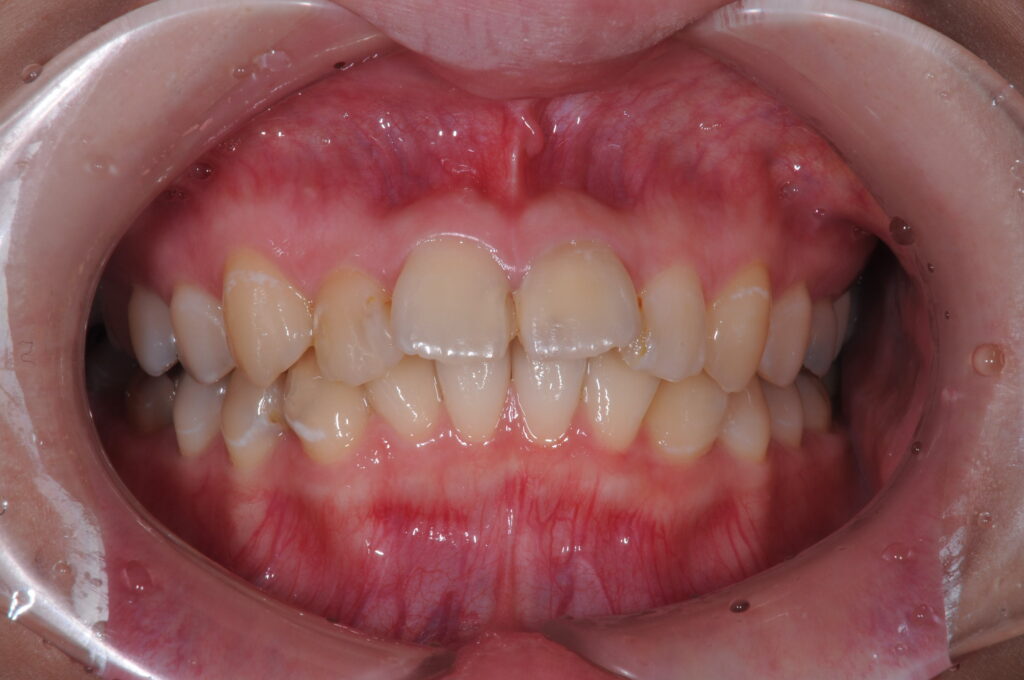

ガタガタの前歯を治したい(20代)セラミック修復・ダイレクトボンディング・ホワイトニング

ガタガタの前歯を治したい(20代)セラミック修復・ダ…

年齢 24歳 性別 女性 初診日 2021年5月 主訴 虫歯治療 治療内容 セラミック修復・ダイレクトボンディング・ホワイトニング 治療期間 4ヶ月 治療費用 約50万円 治療経過 ガタガタの前歯を治したいとのことで来院された。 本来矯正治療の適応であるが、矯正は費…